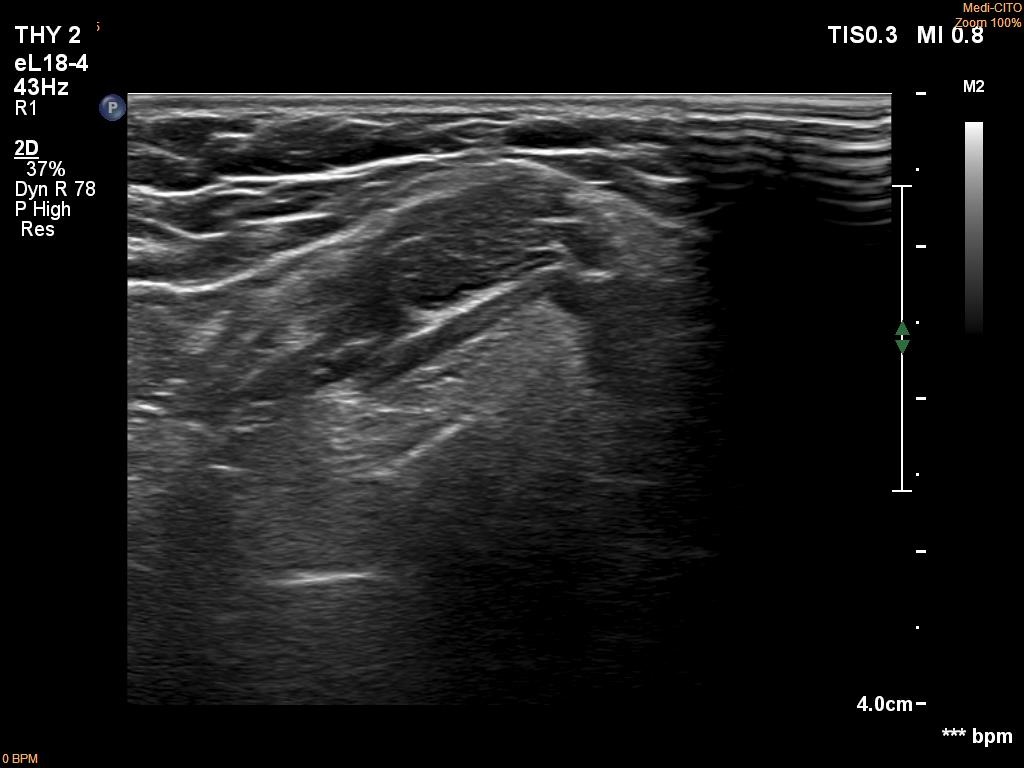

Follow-up investigation 6 months after first visit (ultrasonographic picture 5)

Middle part of the neck, 4 cm above the thyroid, another longitudinal scan. The presentation of this ectopic tissue is very close to that of the thyroid before the surgery.